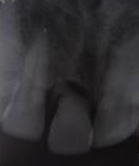

Use of Bone Graft & GTR membrane for an Implant

Pre Operation X-ray